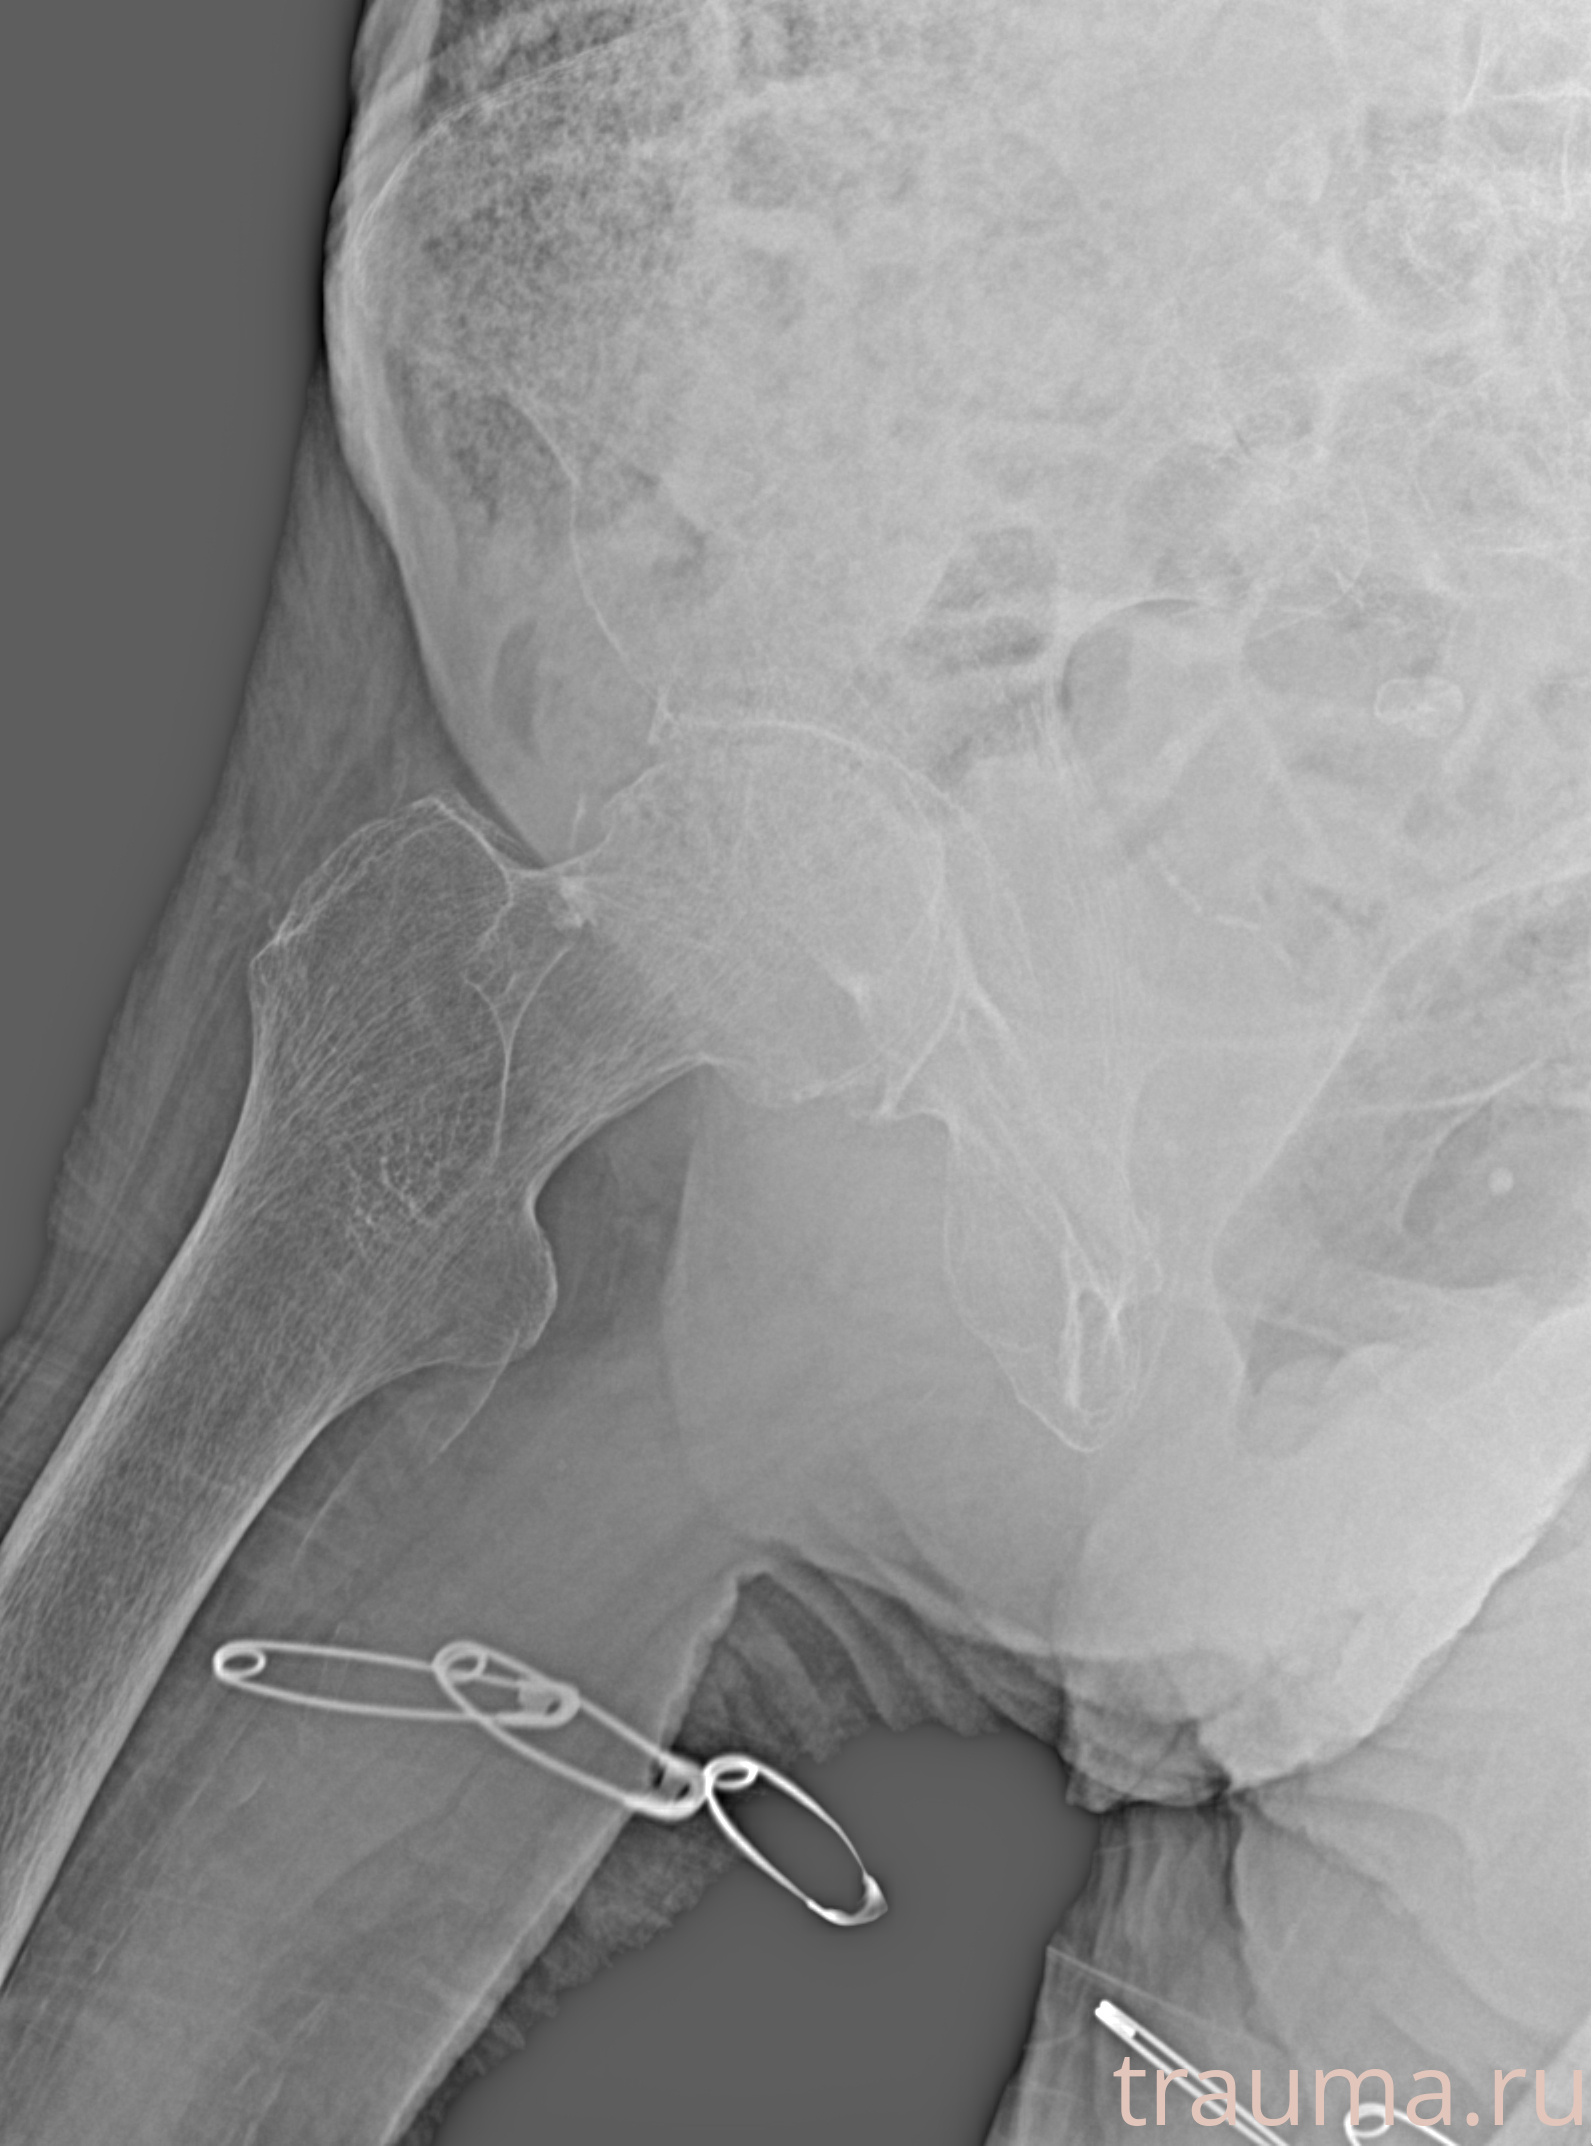

Рентген на дому: по вашему адресу приезжает врач-рентгенолог, травматолог-ортопед с мобильным рентгеновским аппаратом, проводит диагностику травмы или заболевания, делает необходимые рентгенограммы, дает рекомендации по дальнейшему лечению. Получить качественные снимки в домашних условиях возможно благодаря уникальной методике, разработанной МосРентген Центром для института  Склифосовского